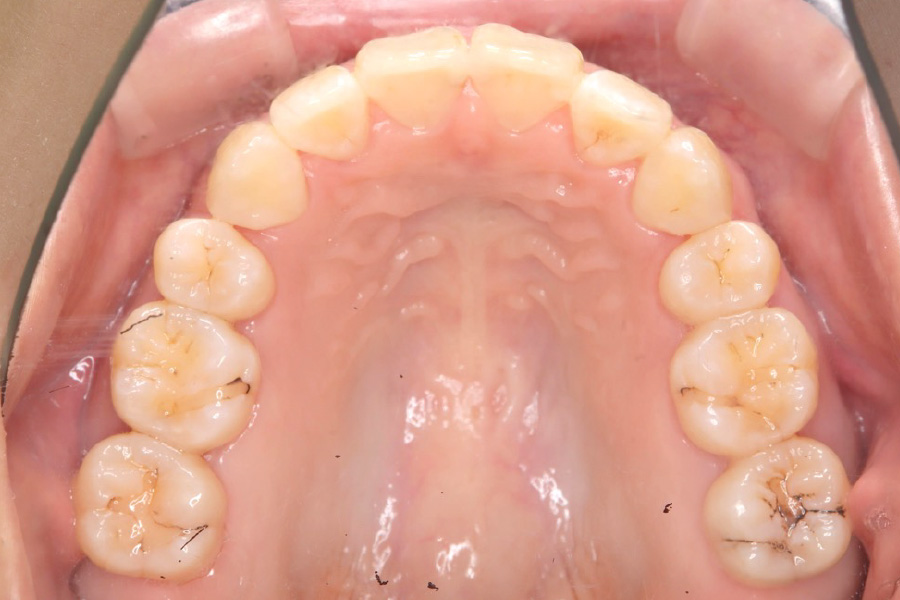

治療後

治療内容 インビザライン矯正

小臼歯抜歯

治療に伴うリスク 矯正終了後は、リテーナーを指示通りに使用し、歯の後戻りを防ぐ必要があります。